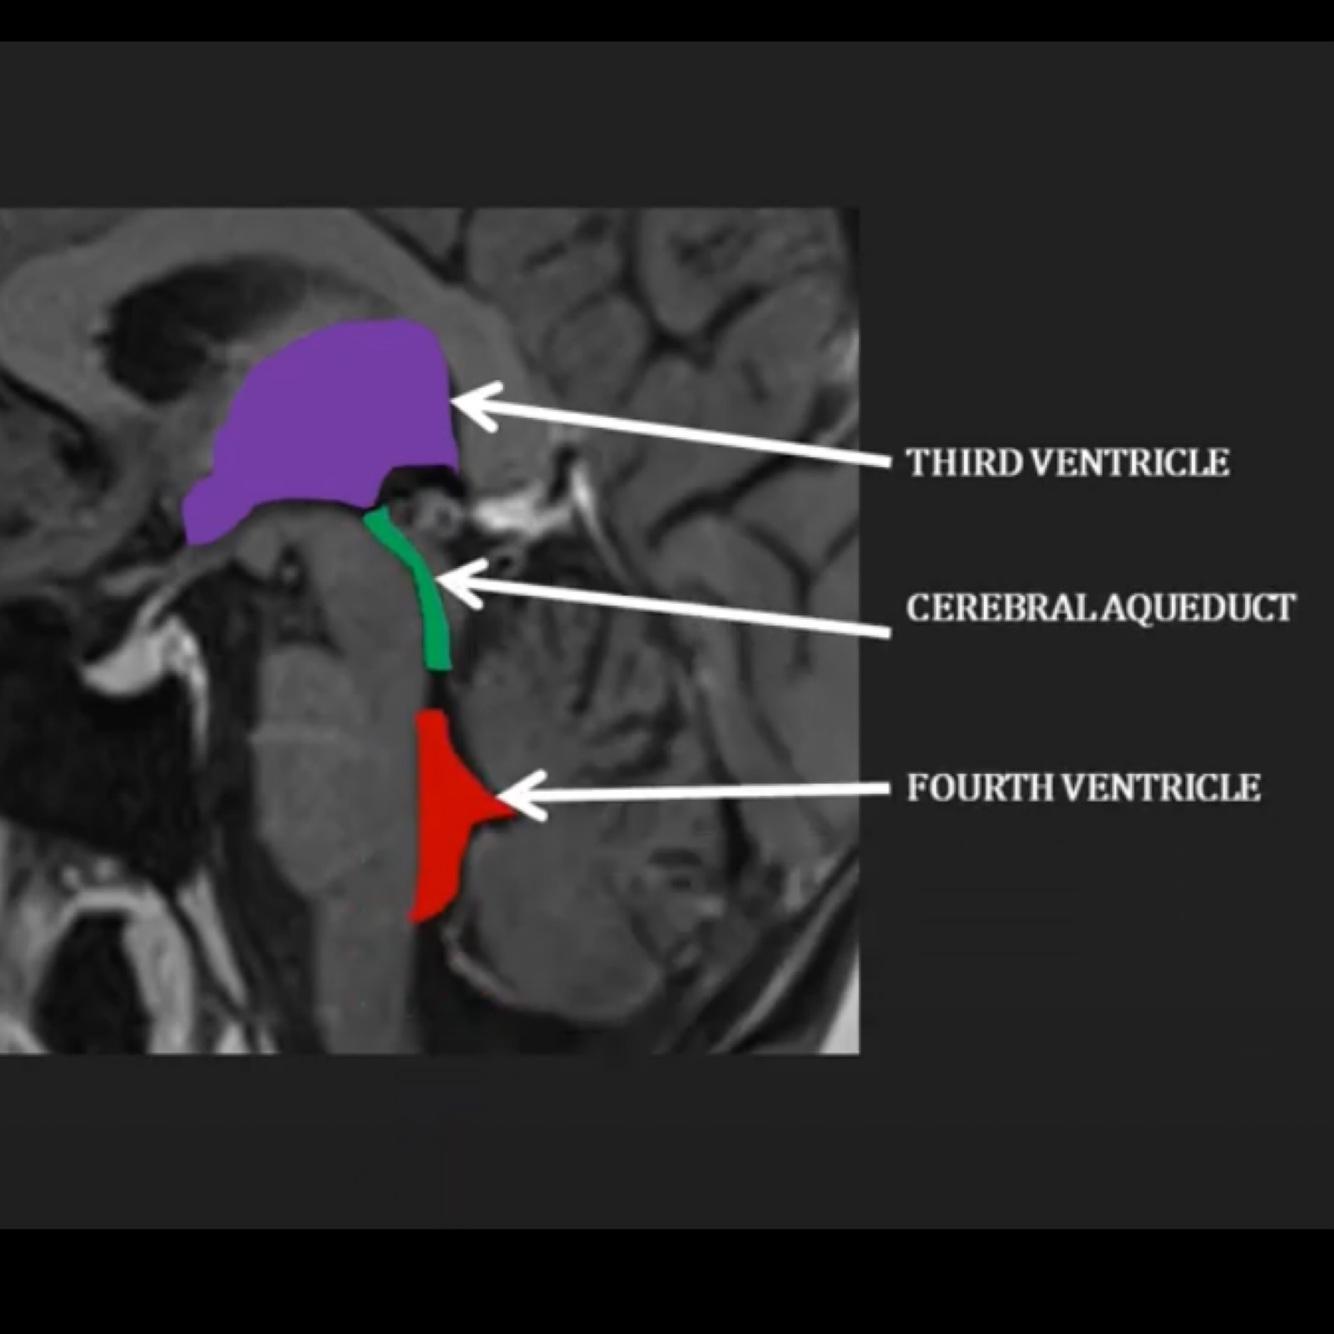

Where does the CSF flow through the brain as visible on this diagram?

A

Through the third ventricle into the cerebral aqueduct, into the fourth ventricle